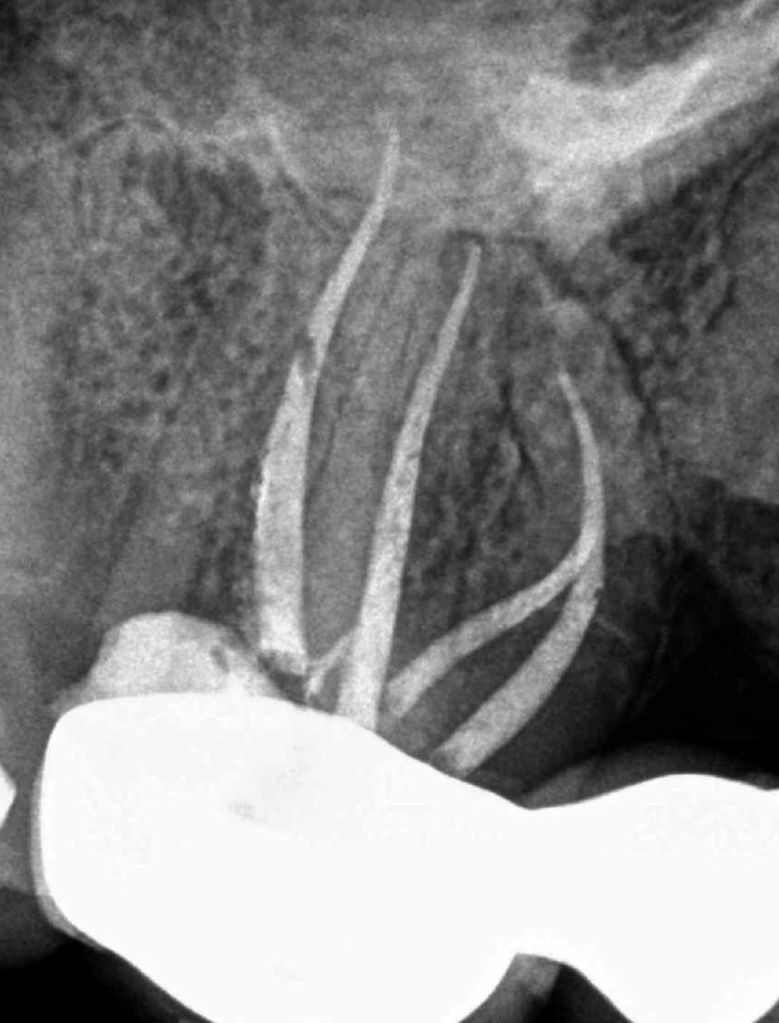

Molar superior anatomía compleja